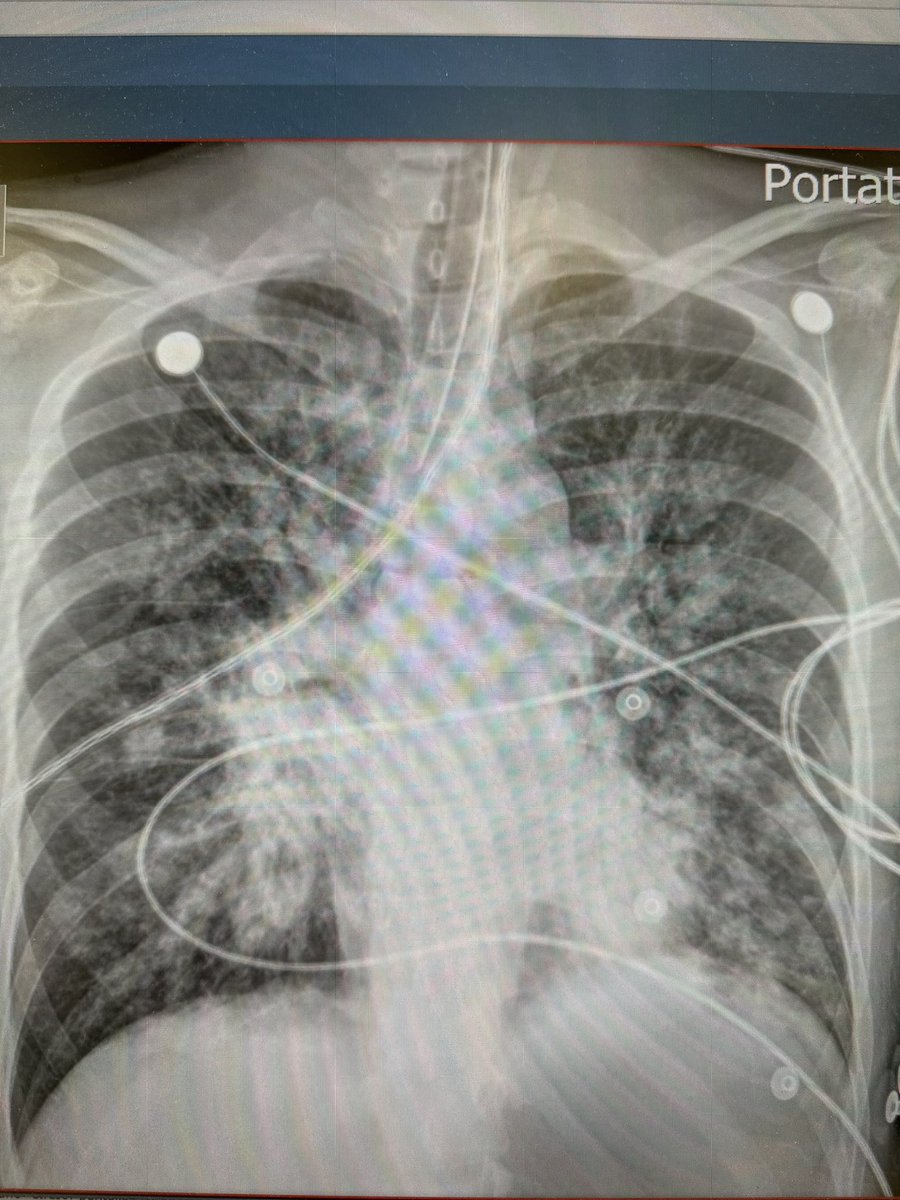

Femenina 46 años ca laringeo tratado con quimioterapia y radioterapia. Actualmente solo dilataciones esófagica programadas. Ingreso a reanimador por disnea 2 días CC - taquipneica, estridor laringeo, sat 50% - Fc 45Xmin. Intubacion crash Bougie, tubo 6.5, con cirujana preparada.